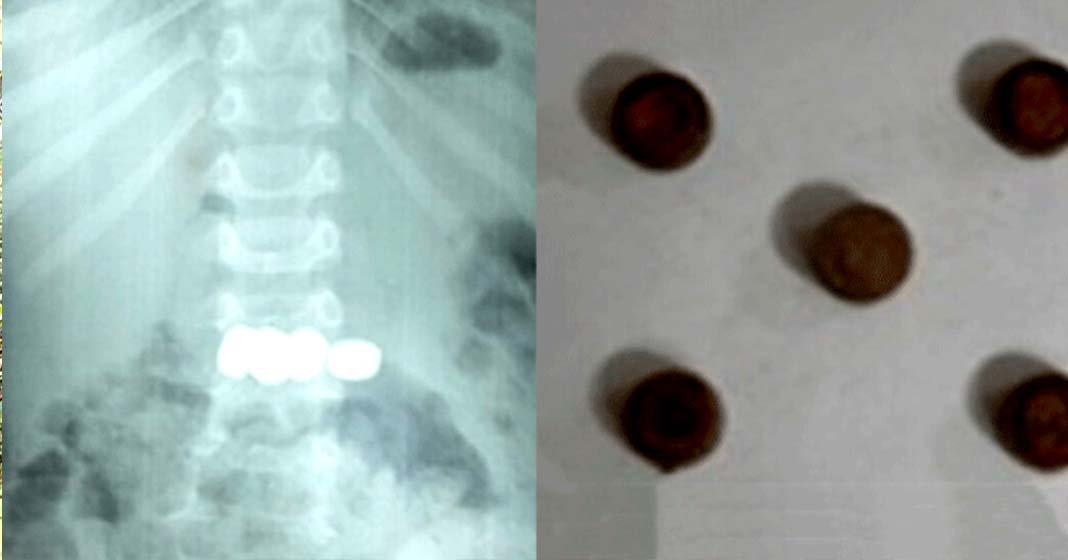

കളിപ്പാട്ടത്തിൽ നിന്നെടുത്ത അഞ്ച് കോയിൻ ടൈപ്പ് ബാറ്ററികൾ വിഴുങ്ങി രണ്ടുവയസുകാരൻ

വയനാട്: മേപ്പാടിയിൽ കളിപ്പാട്ടത്തിൽ നിന്നെടുത്ത അഞ്ച് കോയിൻ ടൈപ്പ് ബാറ്ററികൾ വിഴുങ്ങിയ രണ്ട് വയസ്സുകാരനെ സമയബന്ധിതമായ ചികിത്സയിലൂടെ രക്ഷപ്പെടുത്തി.

വലിയ ആശങ്ക സൃഷ്ടിച്ച സംഭവത്തിൽ എൻഡോസ്കോപ്പി വഴി ബാറ്ററികൾ വിജയകരമായി പുറത്തെടുത്തതോടെ കുട്ടി അപകടനില തരണം ചെയ്തു.

ഗാസ്ട്രോ എന്ററോളജി വിഭാഗം സ്പെഷലിസ്റ്റ് ഡോ. സൂര്യനാരായണയുടെ നേതൃത്വത്തിലാണ് എൻഡോസ്കോപ്പി നടത്തിയത്. പരിശോധനയിൽ കുട്ടിയുടെ ആമാശയത്തിൽ ബാറ്ററികൾ കുടുങ്ങിയതായി കണ്ടെത്തി.

ഏറെ സൂക്ഷ്മതയോടെ നടത്തിയ എൻഡോസ്കോപ്പിക് പ്രക്രിയയിലൂടെ അഞ്ച് ബാറ്ററികളും സുരക്ഷിതമായി പുറത്തെടുക്കാൻ സാധിച്ചു.